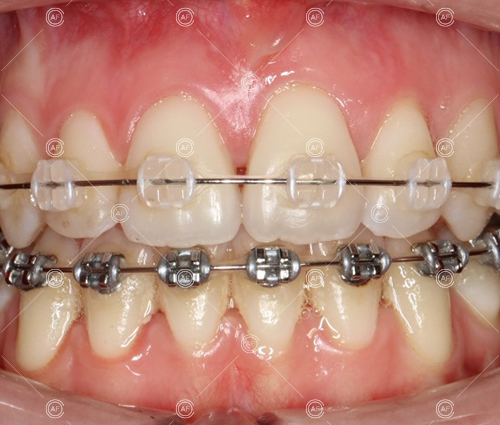

This patient (MH) began her active orthodontic treatment in October 2019 at almost 13 years old. She was unhappy with the appearance of her upper and lower teeth, and especially concerned about the unsightly nature of the high and buccally positioned upper left canine.

about this case…MH presented with class 1 incisors on the class 1 skeletal base with a slightly increased vertical proportion. She had severe crowding in the upper arch and moderate crowding in the lower. Due to the crowding in the lower arch, the lower centre line was off to the left by 2mm.

Treatment progressed by starting with thin, flexible nickel titanium archwires of a round diameter, transitioning to a rectangular nickel titanium archwire before eventually working up to a working archwire (1925 stainless steel).